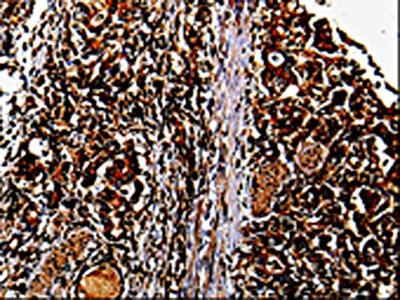

The image is immunohistochemistry of paraffin-embedded Human liver cancer tissue using CSB-PA797584(MMP13 Antibody) at dilution 1/10. (Original magnification: ×200)

The image is immunohistochemistry of paraffin-embedded Human stomach cancer tissue using CSB-PA797584(MMP13 Antibody) at dilution 1/10. (Original magnification: ×200)